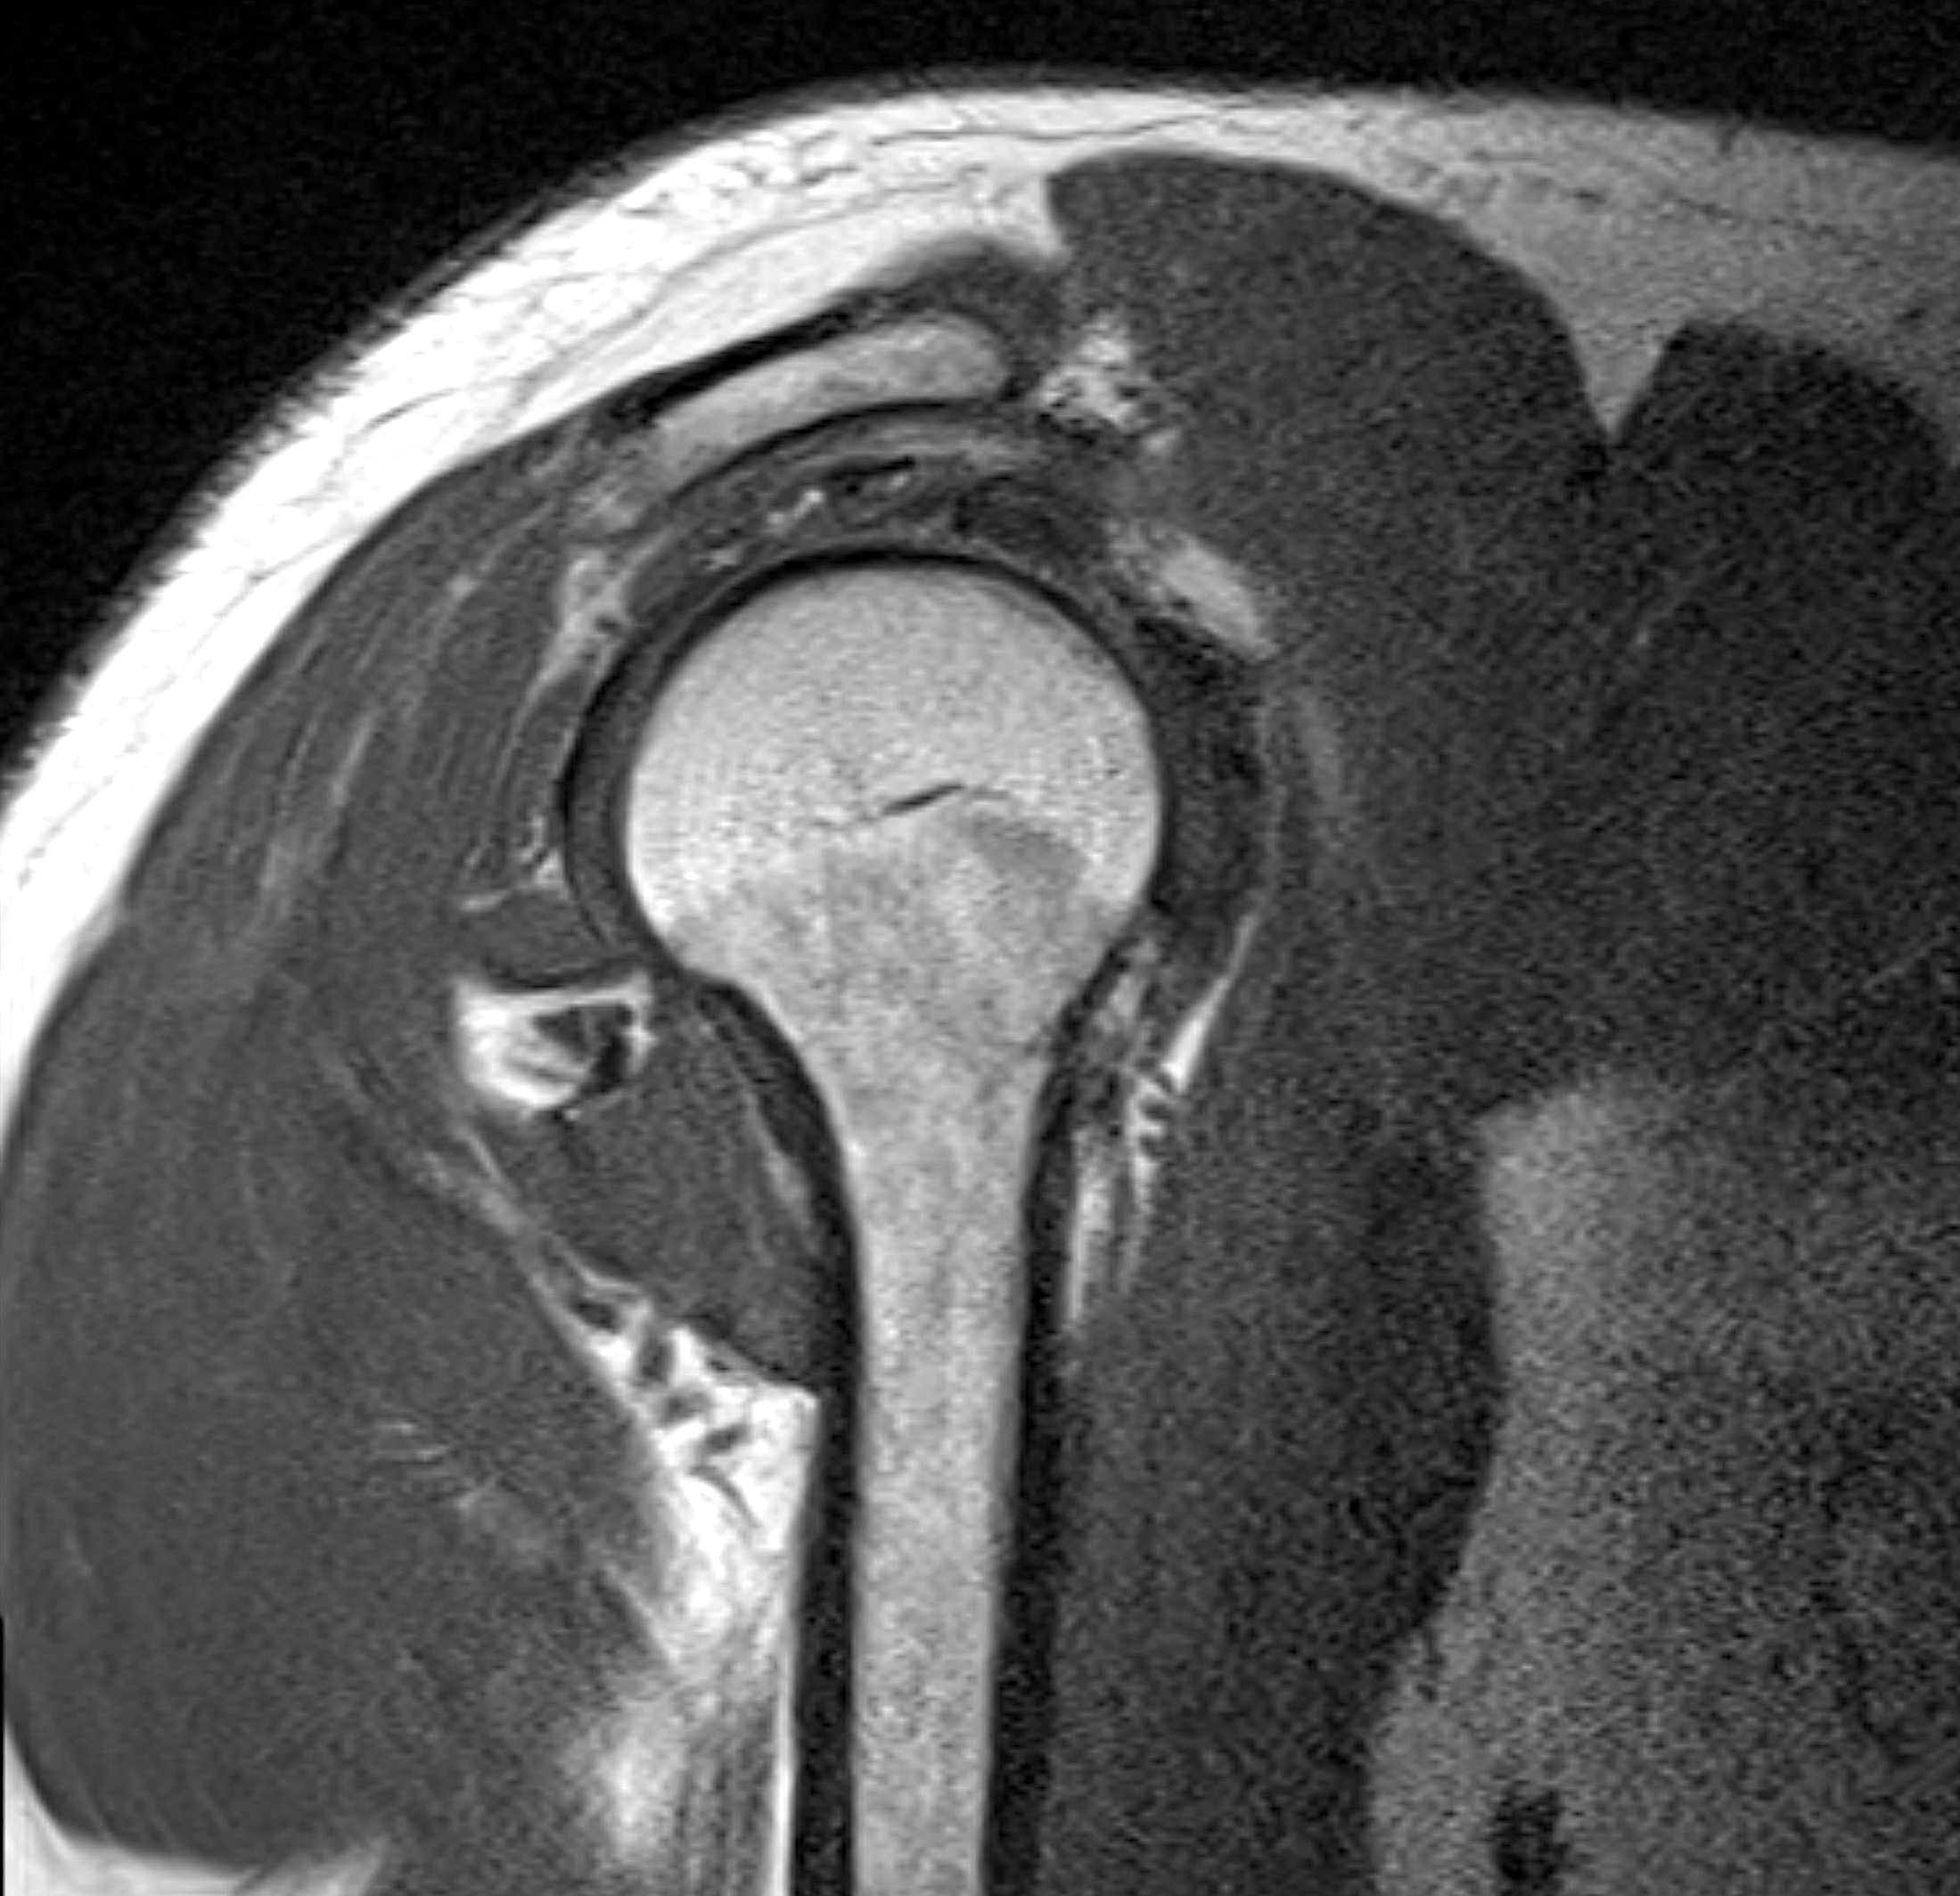

Med en magnetkameraundersökning (MR) av axeln får du en mycket detaljerad bild av ledens inre strukturer, inklusive rotatorkuffens senor, ledkapsel, labrum, brosk och mjukdelar. MR är smärtfri, helt utan strålning och ger en överlägsen bilddiagnostik vid komplexa axelbesvär – särskilt när tidigare undersökningar inte gett tydliga svar.

MR är också särskilt användbart inför kirurgi, för att bedöma omfattningen av skador eller inflammation, och vid misstanke om djupare ledengagemang som inte kan ses med ultraljud eller röntgen.